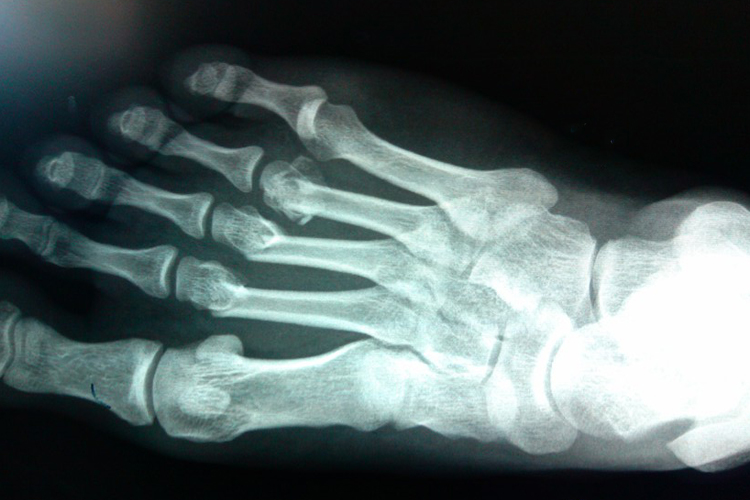

右脚第二三四跖骨骨折是足部较常见的跖骨骨折,骨折的部位可以发生于基底部、骨干及骨颈部。因跖骨相互支持,骨折移位多不明显。发生骨折后足背肿胀、疼痛,皮下有瘀斑,活动功能障碍,局部压痛,并有纵向叩击痛。

发生右脚第二三四跖骨骨折时,若无明显移位,可外敷消炎散,用足底托板加足背扇面形夹板或石膏托、树脂绷带等外固定;若有移位骨折,可根据病情采用手法整复外固定;若程度较重,可在医生指导下通过手术,进行切开复位内固定。